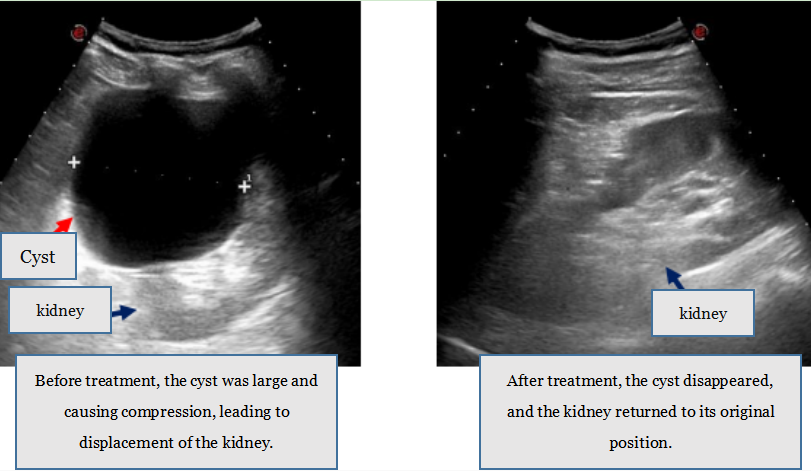

1. Cyst Sclerotherapy